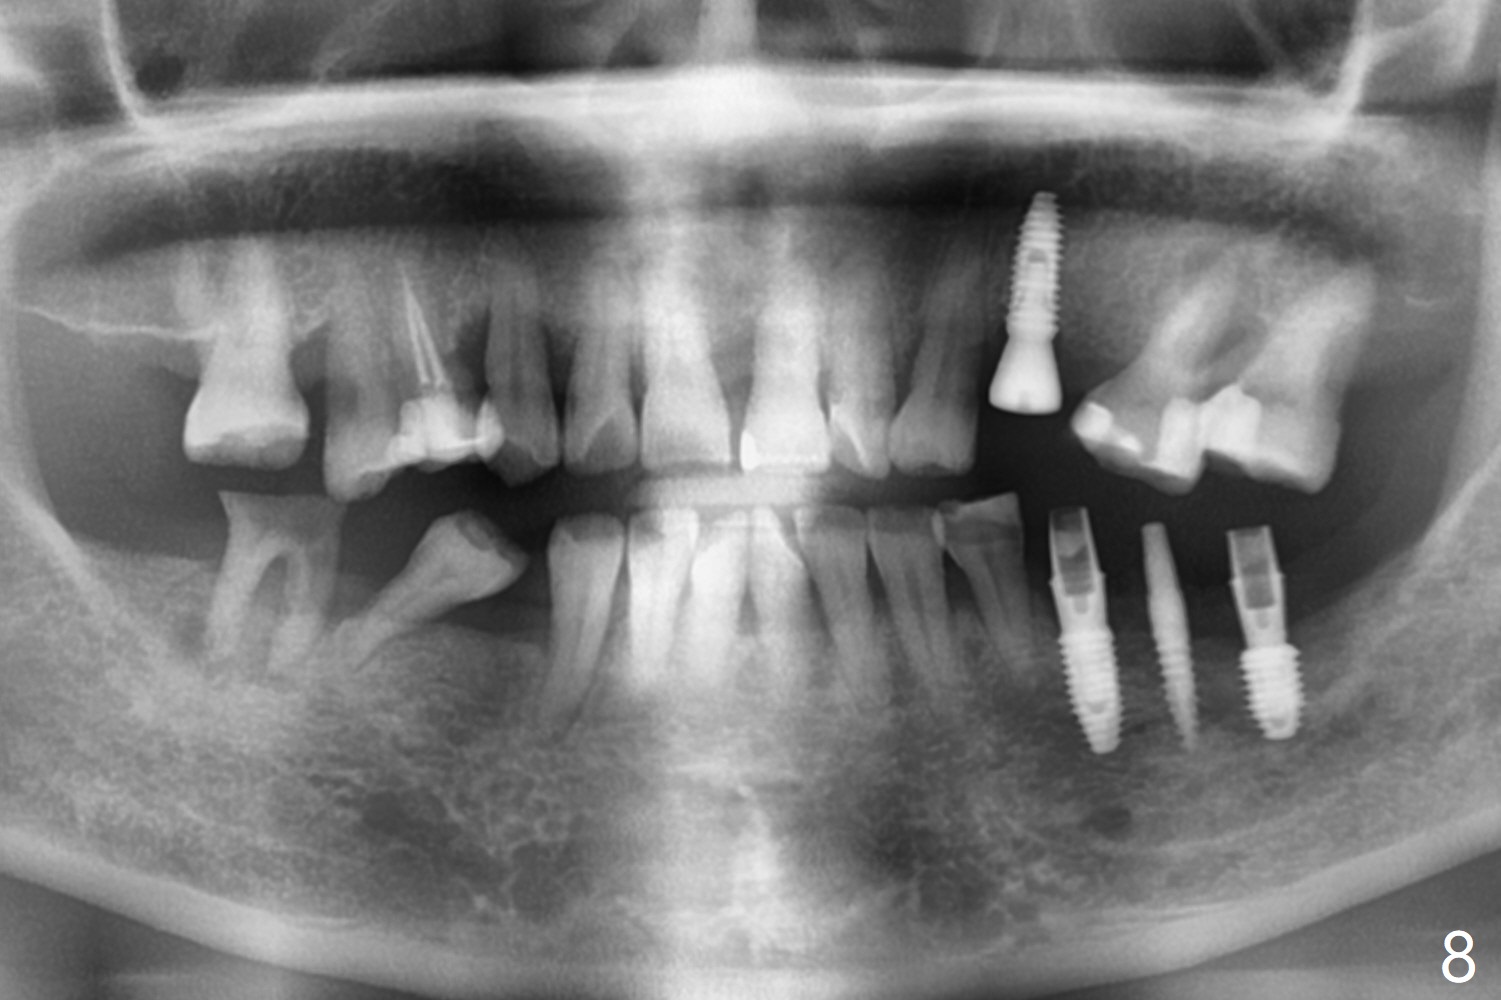

PA is taken after a 2.2 mm drill reaches the depth at #12, since osteotomy is initiated in the mesial slope of the socket (Fig.1 red dashed line) and the neighboring root (*) slightly curves distal. A 8.6x5 mm healing abutment is used to close the socket with the large mesiodistal space after bone graft (Fig.2 *). In contrast, the socket at #20 is large; a 4.5x4.5(3) mm cementation abutment is placed for an immediate provisional to keep autogenous bone (harvested from the site of #18) in place (Fig.3). Six months postop, the patient does not want implant FPD. She wants an additional implant at #19. Since the space between the implants #18 and 20 is 9.41 mm, a narrow implant is indicated (3 or 3.5 mm, Fig.4), in spite of the sufficient buccolingual width (Fig.5). The position and trajectory of the 1.2 mm initial drill and 3x10(2) mm 1-piece implant are acceptable with free hand (Fig.6,7). After 3-4 more turns, panoramic X-ray (Fig.8) and CT (Fig.9) are taken for 28-30 guide. It appears that the 1-piece implant is placed acceptable buccolingual (Fig.9 B). The implants at #12,18,20 (4.5 months postop with guide) are shown in Fig.10-12. It appears that guided surgery is superior in buccolingual position and trajectory to free hand. There is crestal remodeling without implant thread exposure 11 months postop (Fig.13).